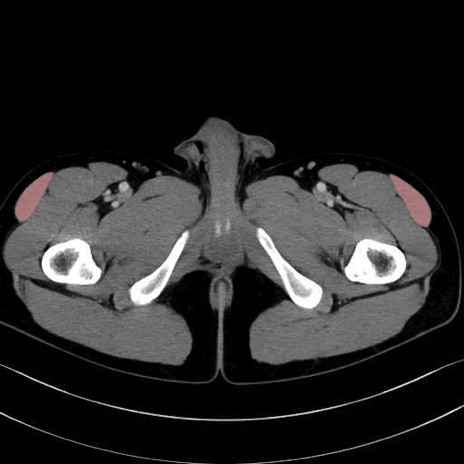

大腿筋膜張筋 (Tensor fasciae latae)